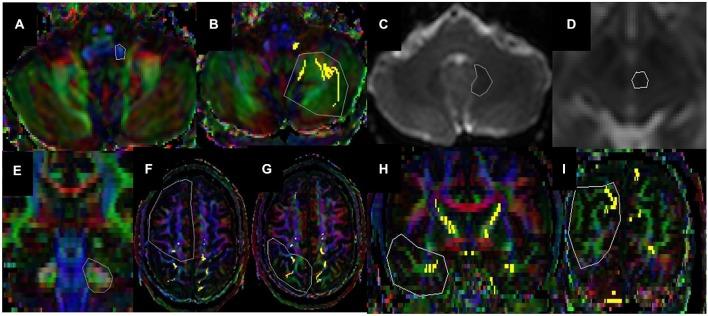

Cerebellar white matter (WM) connections to the central nervous system are classified functionally into the Spinocerebellar (SC), vestibulocerebellar (VC), and cerebrocerebellar subdivisions. The SC pathways project from spinal cord to cerebellum, whereas the VC pathways project from vestibular organs of the inner ear. Cerebrocerebellar connections are composed of feed forward and feedback connections between cerebrum and cerebellum including the cortico-ponto-cerebellar (CPC) pathways being of cortical origin and the dentate-rubro-thalamo-cortical (DRTC) pathway being of cerebellar origin. In this study we systematically quantified the whole cerebellar system connections using diffusion tensor magnetic resonance imaging (DT-MRI). Ten right-handed healthy subjects (7 males and 3 females, age range 20-51 years) were studied. DT-MRI data were acquired with a voxel size = 2 mm × 2 mm × 2 mm at a 3.0 Tesla clinical MRI scanner. The DT-MRI data were prepared and analyzed using anatomically-guided deterministic tractography methods to reconstruct the SC, DRTC, fronto-ponto-cerebellar (FPC), parieto-ponto-cerebellar (PPC), temporo-ponto-cerebellar (TPC) and occipito-ponto-cerebellar (OPC). The DTI-attributes or the cerebellar tracts along with their cortical representation (Brodmann areas) were presented in standard Montréal Neurological Institute space. All cerebellar tract volumes were quantified and correlated with volumes of cerebral cortical, subcortical gray matter (GM), cerebral WM and cerebellar GM, and cerebellar WM. On our healthy cohort, the ratio of total cerebellar GM-to-WM was ~3.29 ± 0.24, whereas the ratio of cerebral GM-to-WM was approximately 1.10 ± 0.11. The sum of all cerebellar tract volumes is ~25.8 ± 7.3 mL, or a percentage of 1.6 ± 0.45 of the total intracranial volume (ICV).

小脑白质(WM)与中枢神经系统的连接在功能上可分为脊髓小脑(SC)、前庭小脑(VC)和大脑小脑亚区。脊髓小脑通路从脊髓投射至小脑,而前庭小脑通路则从内耳的前庭器官投射而来。大脑小脑连接由大脑和小脑之间的前馈和反馈连接组成,包括起源于皮质的皮质 - 脑桥 - 小脑(CPC)通路以及起源于小脑的齿状核 - 红核 - 丘脑 - 皮质(DRTC)通路。在本研究中,我们使用扩散张量磁共振成像(DT - MRI)系统地量化了整个小脑系统的连接。研究了10名右利手健康受试者(7名男性和3名女性,年龄范围20 - 51岁)。DT - MRI数据在3.0特斯拉临床MRI扫描仪上以体素大小 = 2毫米×2毫米×2毫米采集。使用解剖学引导的确定性纤维束成像方法对DT - MRI数据进行处理和分析,以重建脊髓小脑、齿状核 - 红核 - 丘脑 - 皮质、额脑桥小脑(FPC)、顶脑桥小脑(PPC)、颞脑桥小脑(TPC)和枕脑桥小脑(OPC)。DTI属性或小脑纤维束及其皮质代表区(布罗德曼区)以标准的蒙特利尔神经病学研究所空间呈现。对所有小脑纤维束体积进行量化,并与大脑皮质、皮质下灰质(GM)、大脑白质以及小脑灰质和小脑白质的体积进行相关性分析。在我们的健康队列中,小脑灰质与白质的总体积比约为3.29±0.24,而大脑灰质与白质的体积比约为1.10±0.11。所有小脑纤维束体积的总和约为25.8±7.3毫升,占总颅内体积(ICV)的1.6±0.45%。